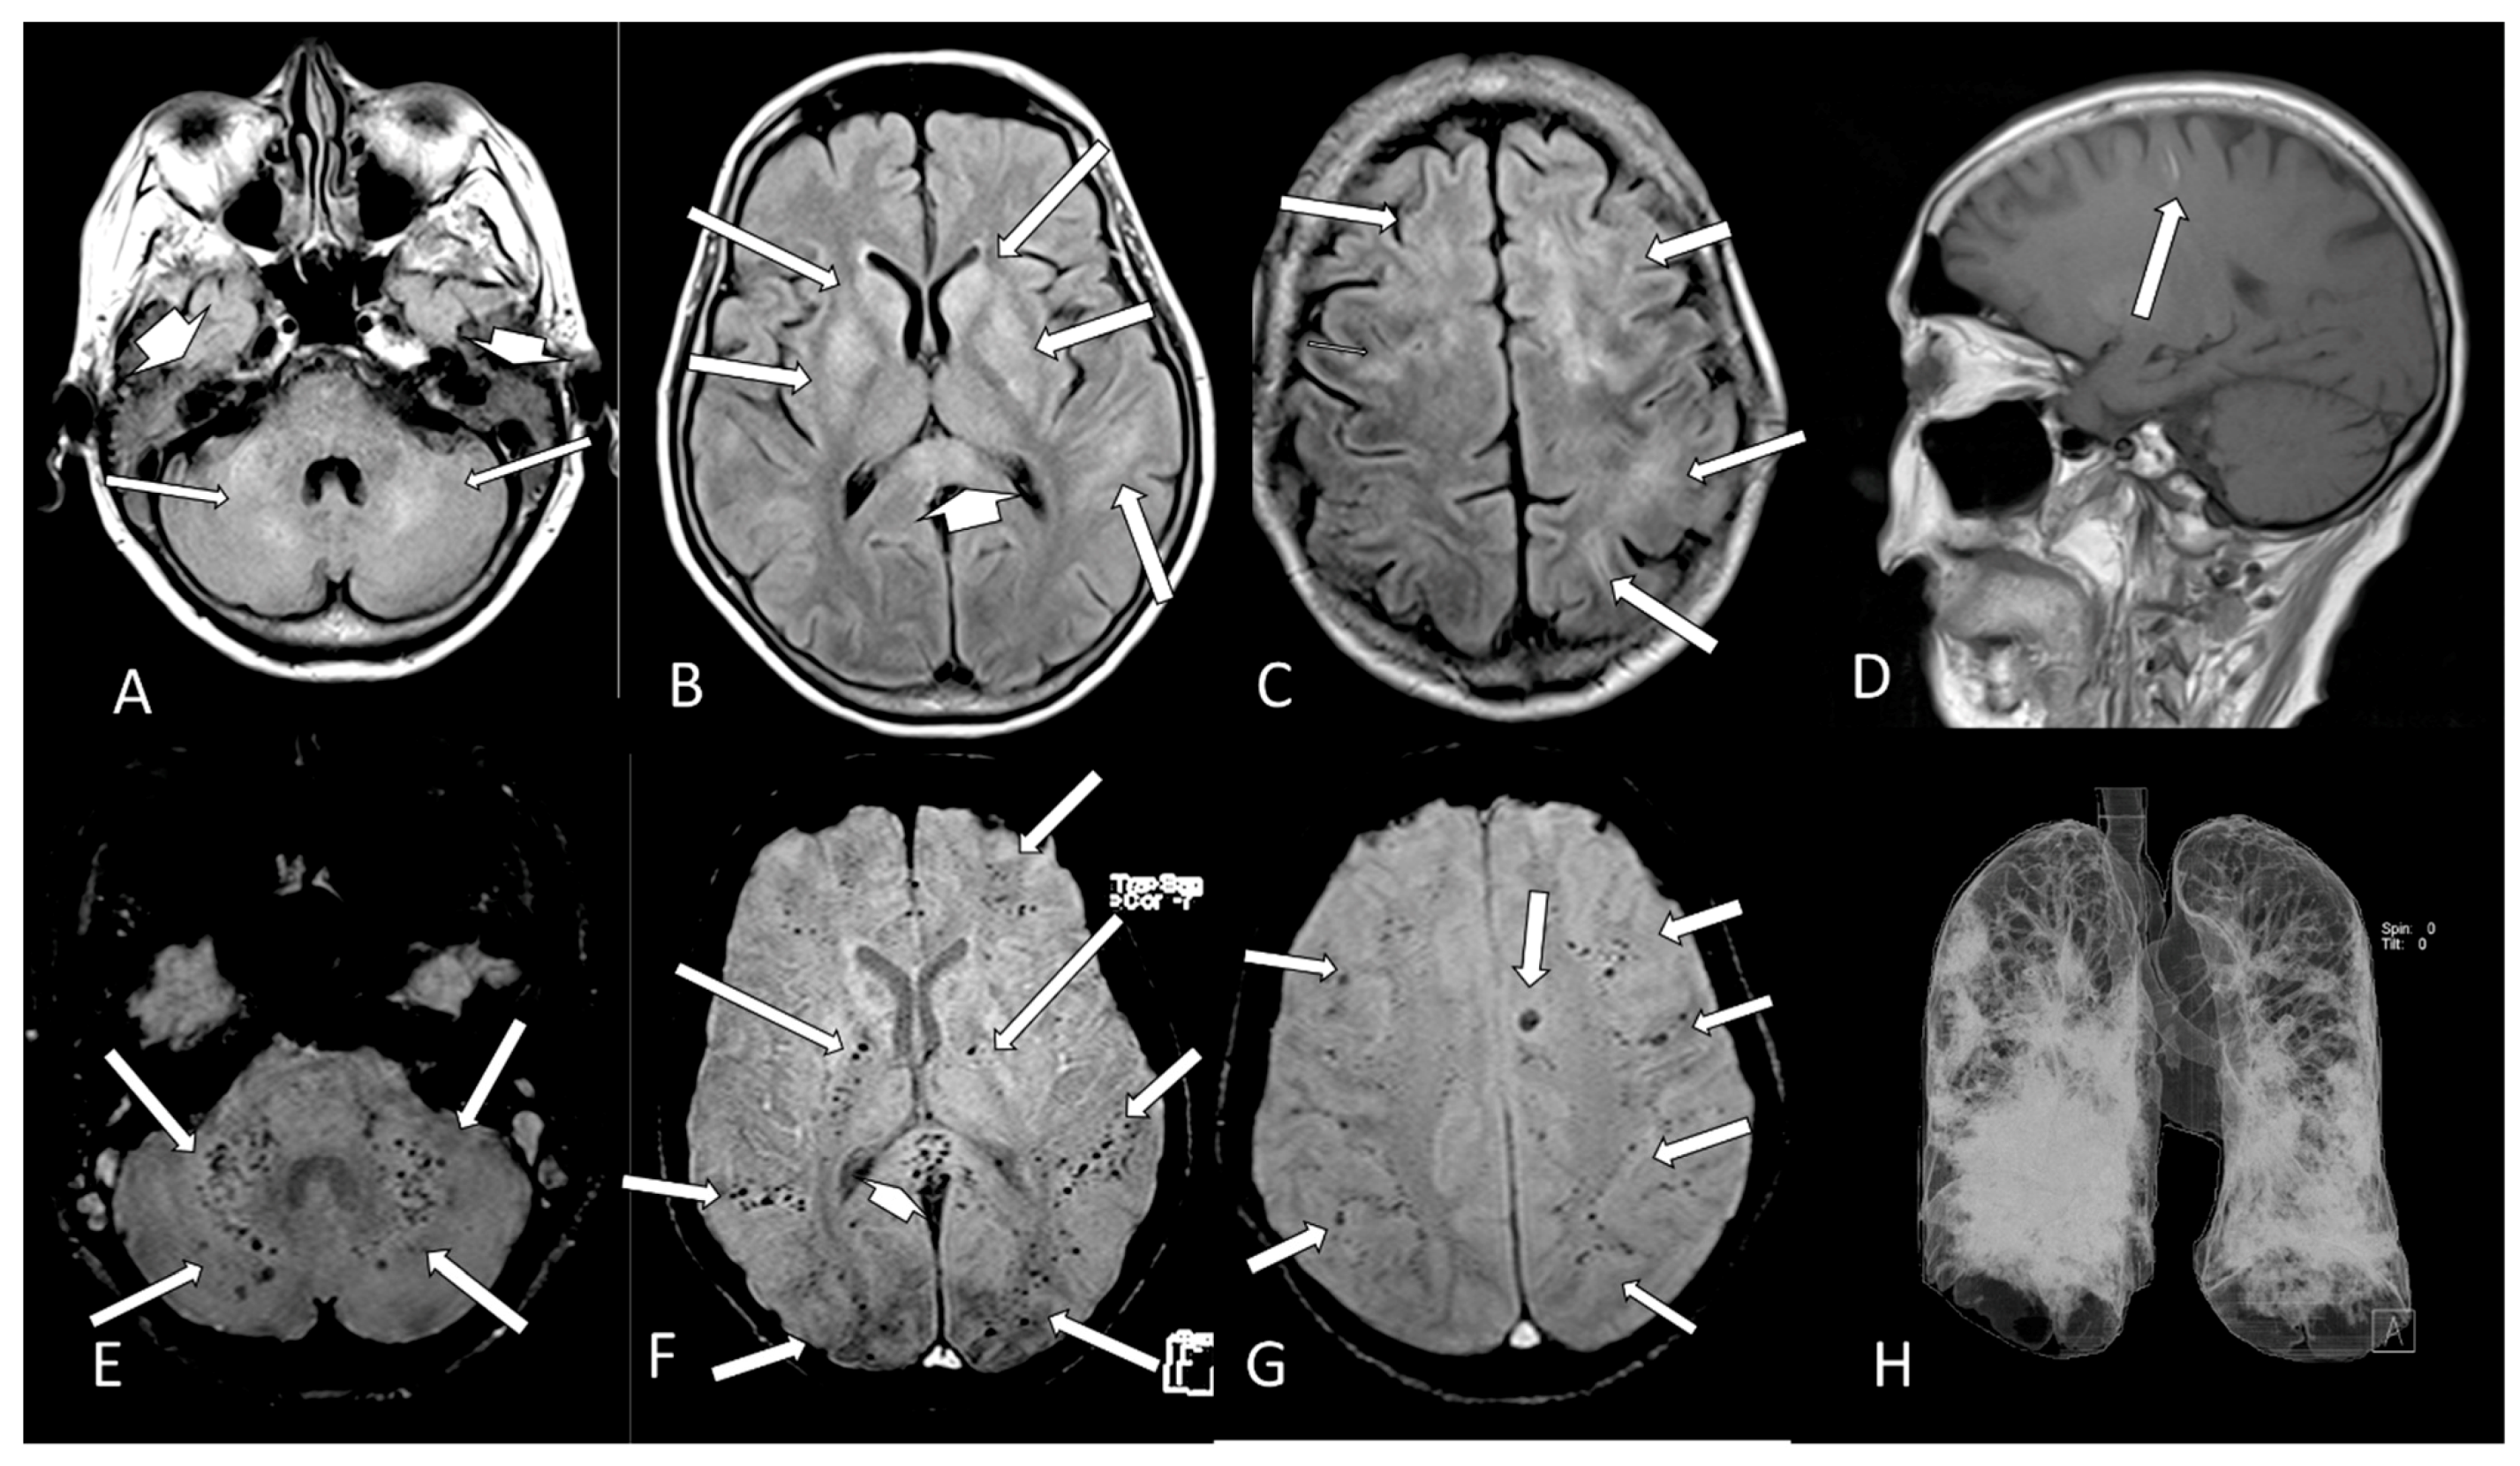

| 15 | M | 26 | seizure, hemiparesis | no | no | no | no | temporo-occipital hypersignal on FLAIR, hemosiderosis (MRI) | >50% | ICU | no | |

| 26 | M | 71 | - | Neurologic sequel | - | - | - | no | parietal subcortical microbleeding (MRI) | >50% | ICU | no |

| 27 | F | 61 | - | headache | - | - | - | no | cortical/subcortical hematomas and pale globes microbleedings + olfactory bulb injury (MRI) | >50% | internal | no |

| 28 | M | 80 | - | seizure, recurrent syncope | yes | yes | yes | O2 catheter | frontal microbleeding and olfactory bulb injury (MRI) | <25% | ICU | no |

| 30 | F | 70 | - | yes | yes | yes | ventilator | microbleedings in base ganglia, brainstem and cerebellum (MRI) | >50% | ICU | yes | |

| 31 | M | 62 | - | coma | yes | yes | yes | ventilator | cerebellum, corpus callosum and parietal white matterbleeding and restricted DWI small lesions (MRI) | >50% | ICU | no |

| 34 | F | 34 | stroke and seizure | - | - | - | - | old ischemic lesion with restricted DWI areas/right middle cerebral artery stenosis/areas of hemorrhage and olfactory bulb injury (MRI) | <25% | external | no | |